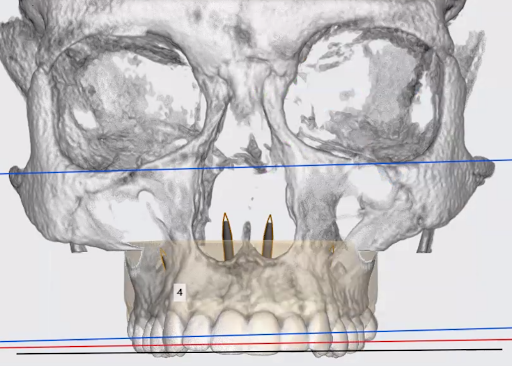

1. 3D Imaging

We begin with a 3D CBCT X-ray, allowing us to see the patient’s skeletal anatomy, airway, and suture maturity with incredible accuracy.

CBCT imaging allows us to diagnose in 3-Dimensions